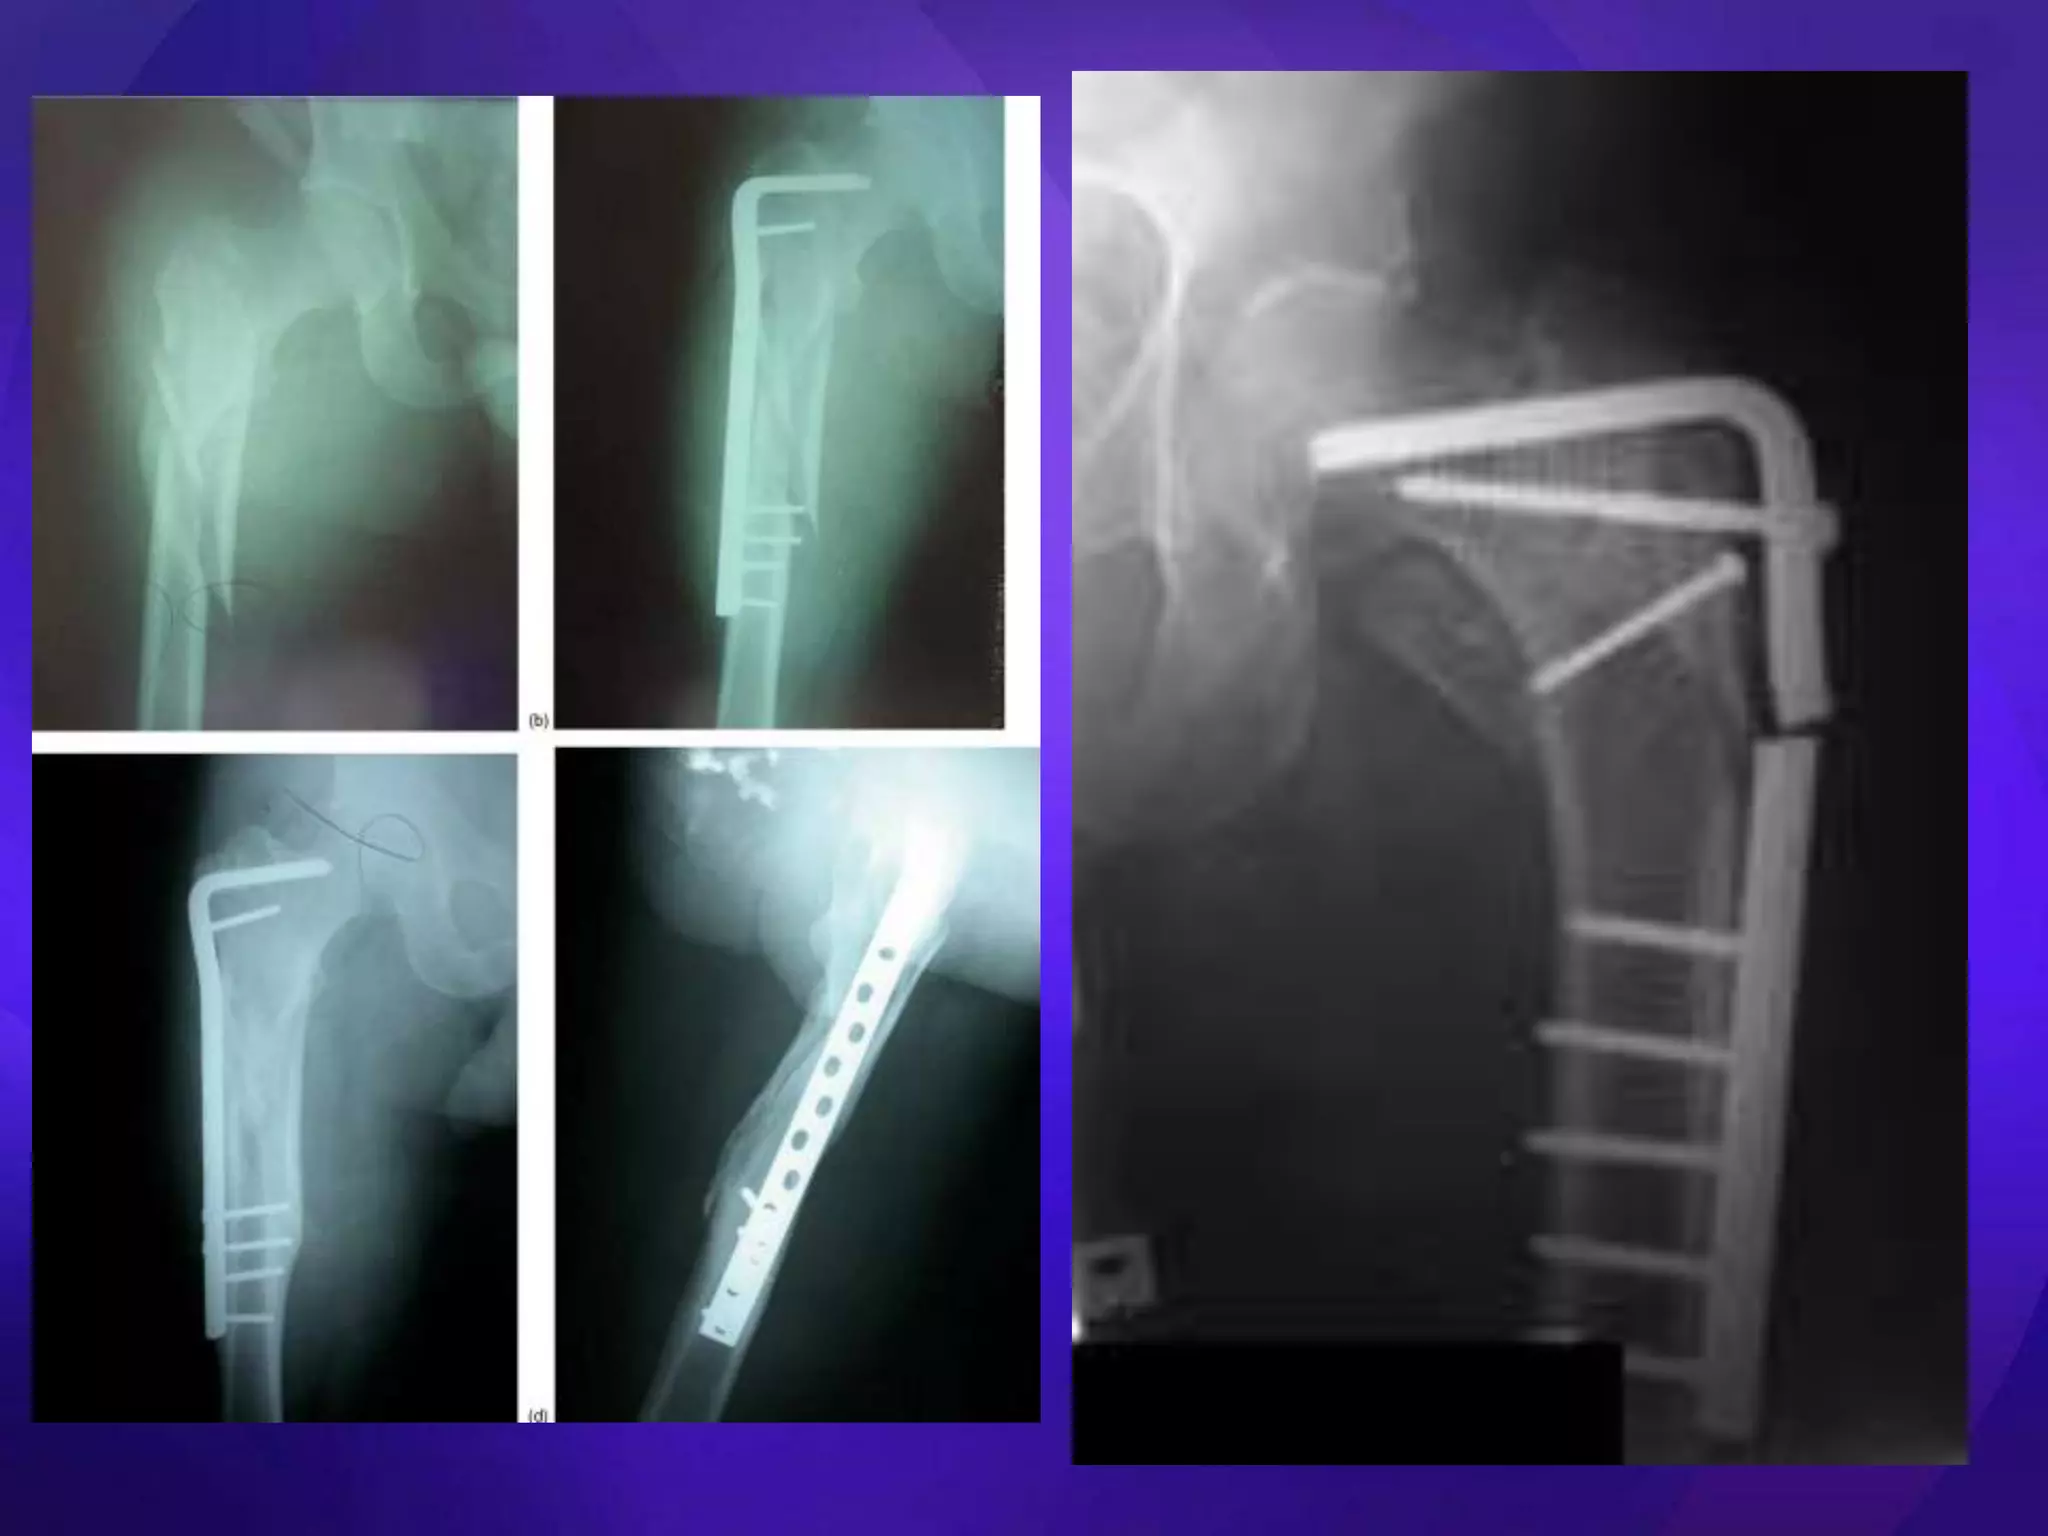

• Extramedullary

– ORIF

– DHS, Medoff Sliding Plate, DCS, blade plate, locking plates

• Intramedullary

– Centromedullary

– Cephalomedullary

– Short vs long